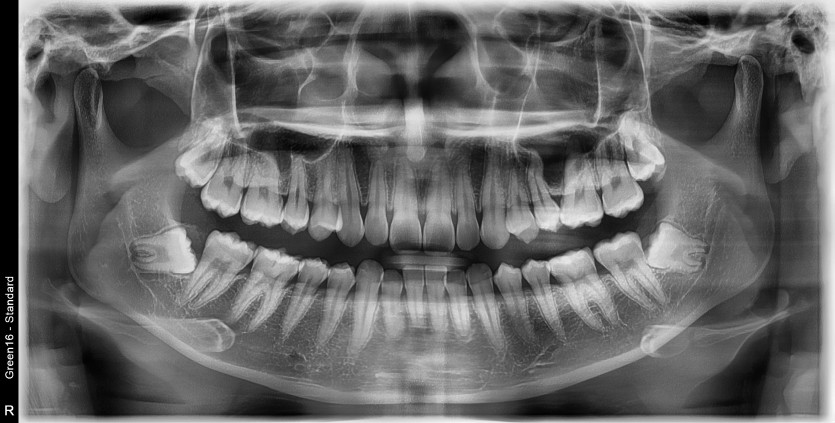

#38,48 사랑니 발치

구강 외과 전문의가 당일 발치했습니다.